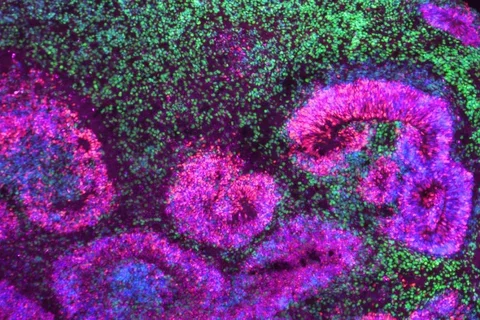

UCLA scientists develop off-the-shelf immunotherapy for metastatic kidney cancer

An off-the-shelf immunotherapy for metastatic kidney cancer uses specially engineered immune cells to attack cancer tumors.